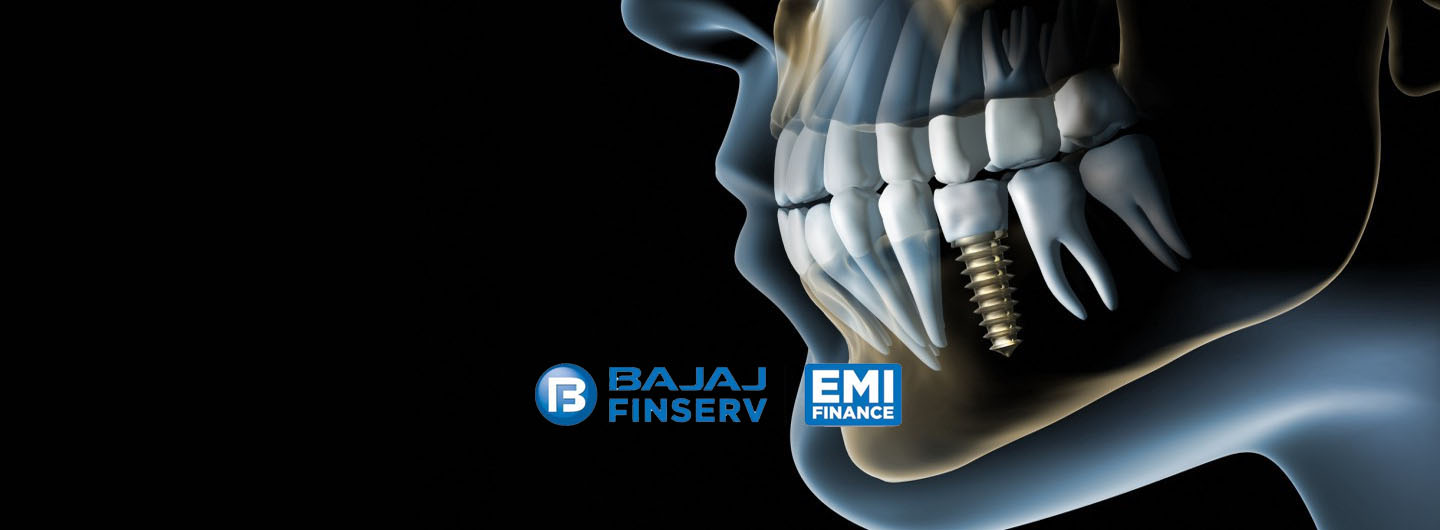

POPULAR DENTAL PROCEDURES